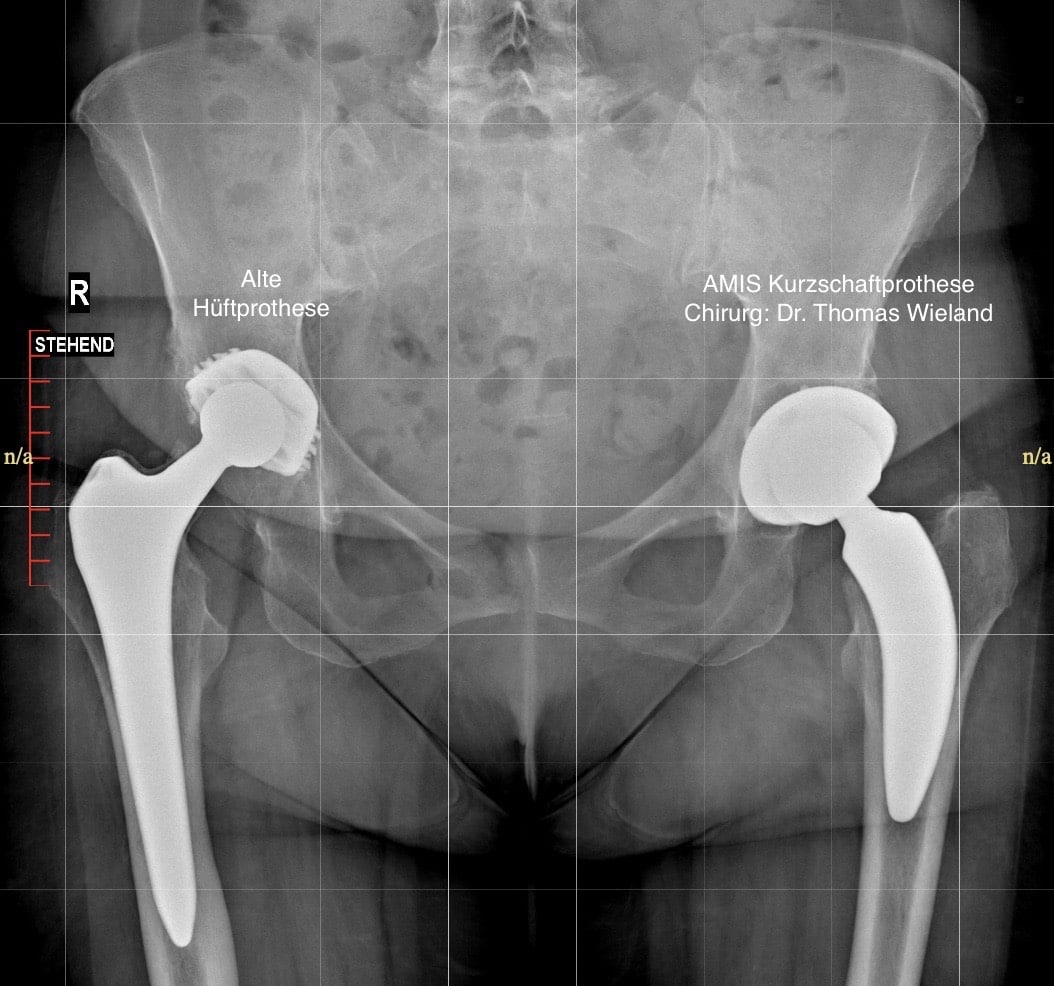

AMIS Hüfte

Diese Operation wird von mir in minimal invasiver Technik (muskelschonend) nach AMIS (Anterior Minimally Invasive Surgery) oder ALMIS (Anteriolateral Minimally Invasive Surgery) durchgeführt. Die AMIS Methode hat den Vorteil, dass zwischen den Muskeln eingegangen wird und somit kein einziger Muskel oder Sehne eingeschnitten werden muss. Dadurch können die Schmerzen nach der Operation erheblich vermindert werden. Die Nachbehandlung und die Mobilisierung erfolgen wesentlich schneller als in der herkömmlichen Technik.